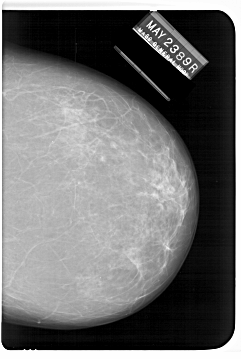

A_1247_1.LEFT_CC

LEFT_CC LINES 6331 PIXELS_PER_LINE 4576 BITS_PER_PIXEL 12 RESOLUTION 43.5 OVERLAY